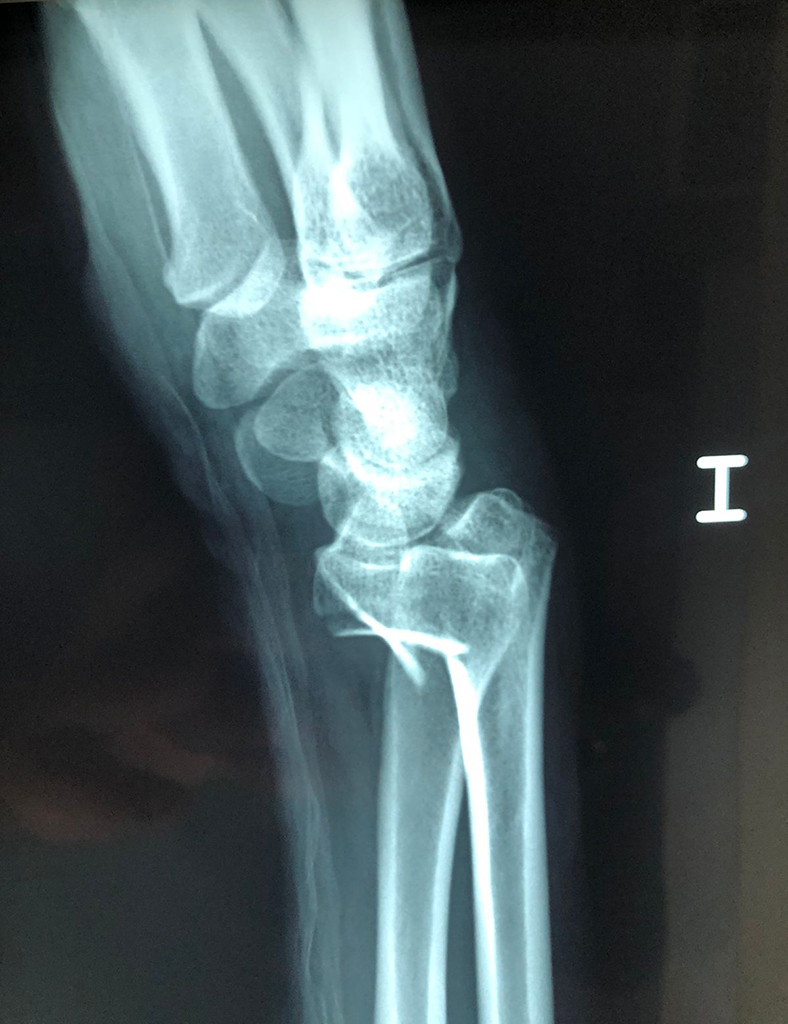

Cirugía de Fémur - Cirugías de Muñecas y Manos

Los procedimientos más comunes en cirugía de la mano son aquellos destinados a reparar traumatismos, incluyendo lesiones de tendones, nervios, vasos sanguíneos, y articulaciones; huesos fracturados; y quemaduras, cortes, y otros daños de la piel.